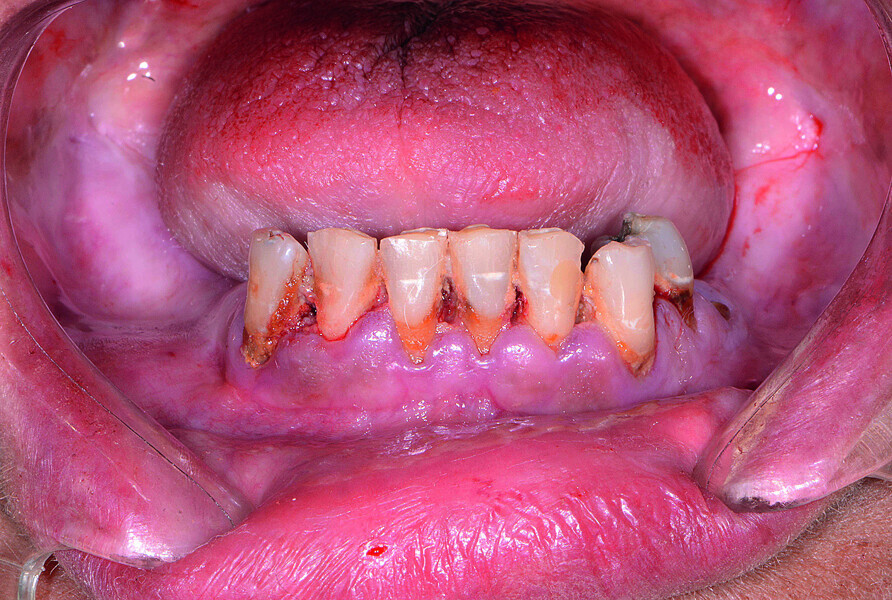

Fig. 2: Pre-op retracted view without denture.